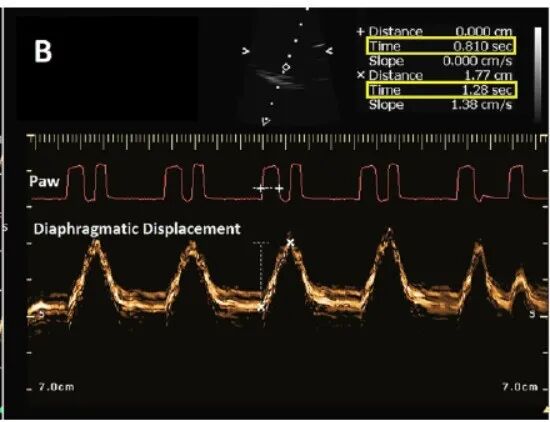

膈肌超声可用于诊断双触发,如下图所示,红色线为压力时间曲线,下方橘红色粗线为膈肌位移图像,通过分析图像可以看出,在单次膈肌位移时间范围内(即吸气时间,图中所示为1.28秒),出现了两次连续的呼吸机送气(第一次送气时间为0.81秒),即患者吸气触发了两次连续的送气,故可判定为双触发。